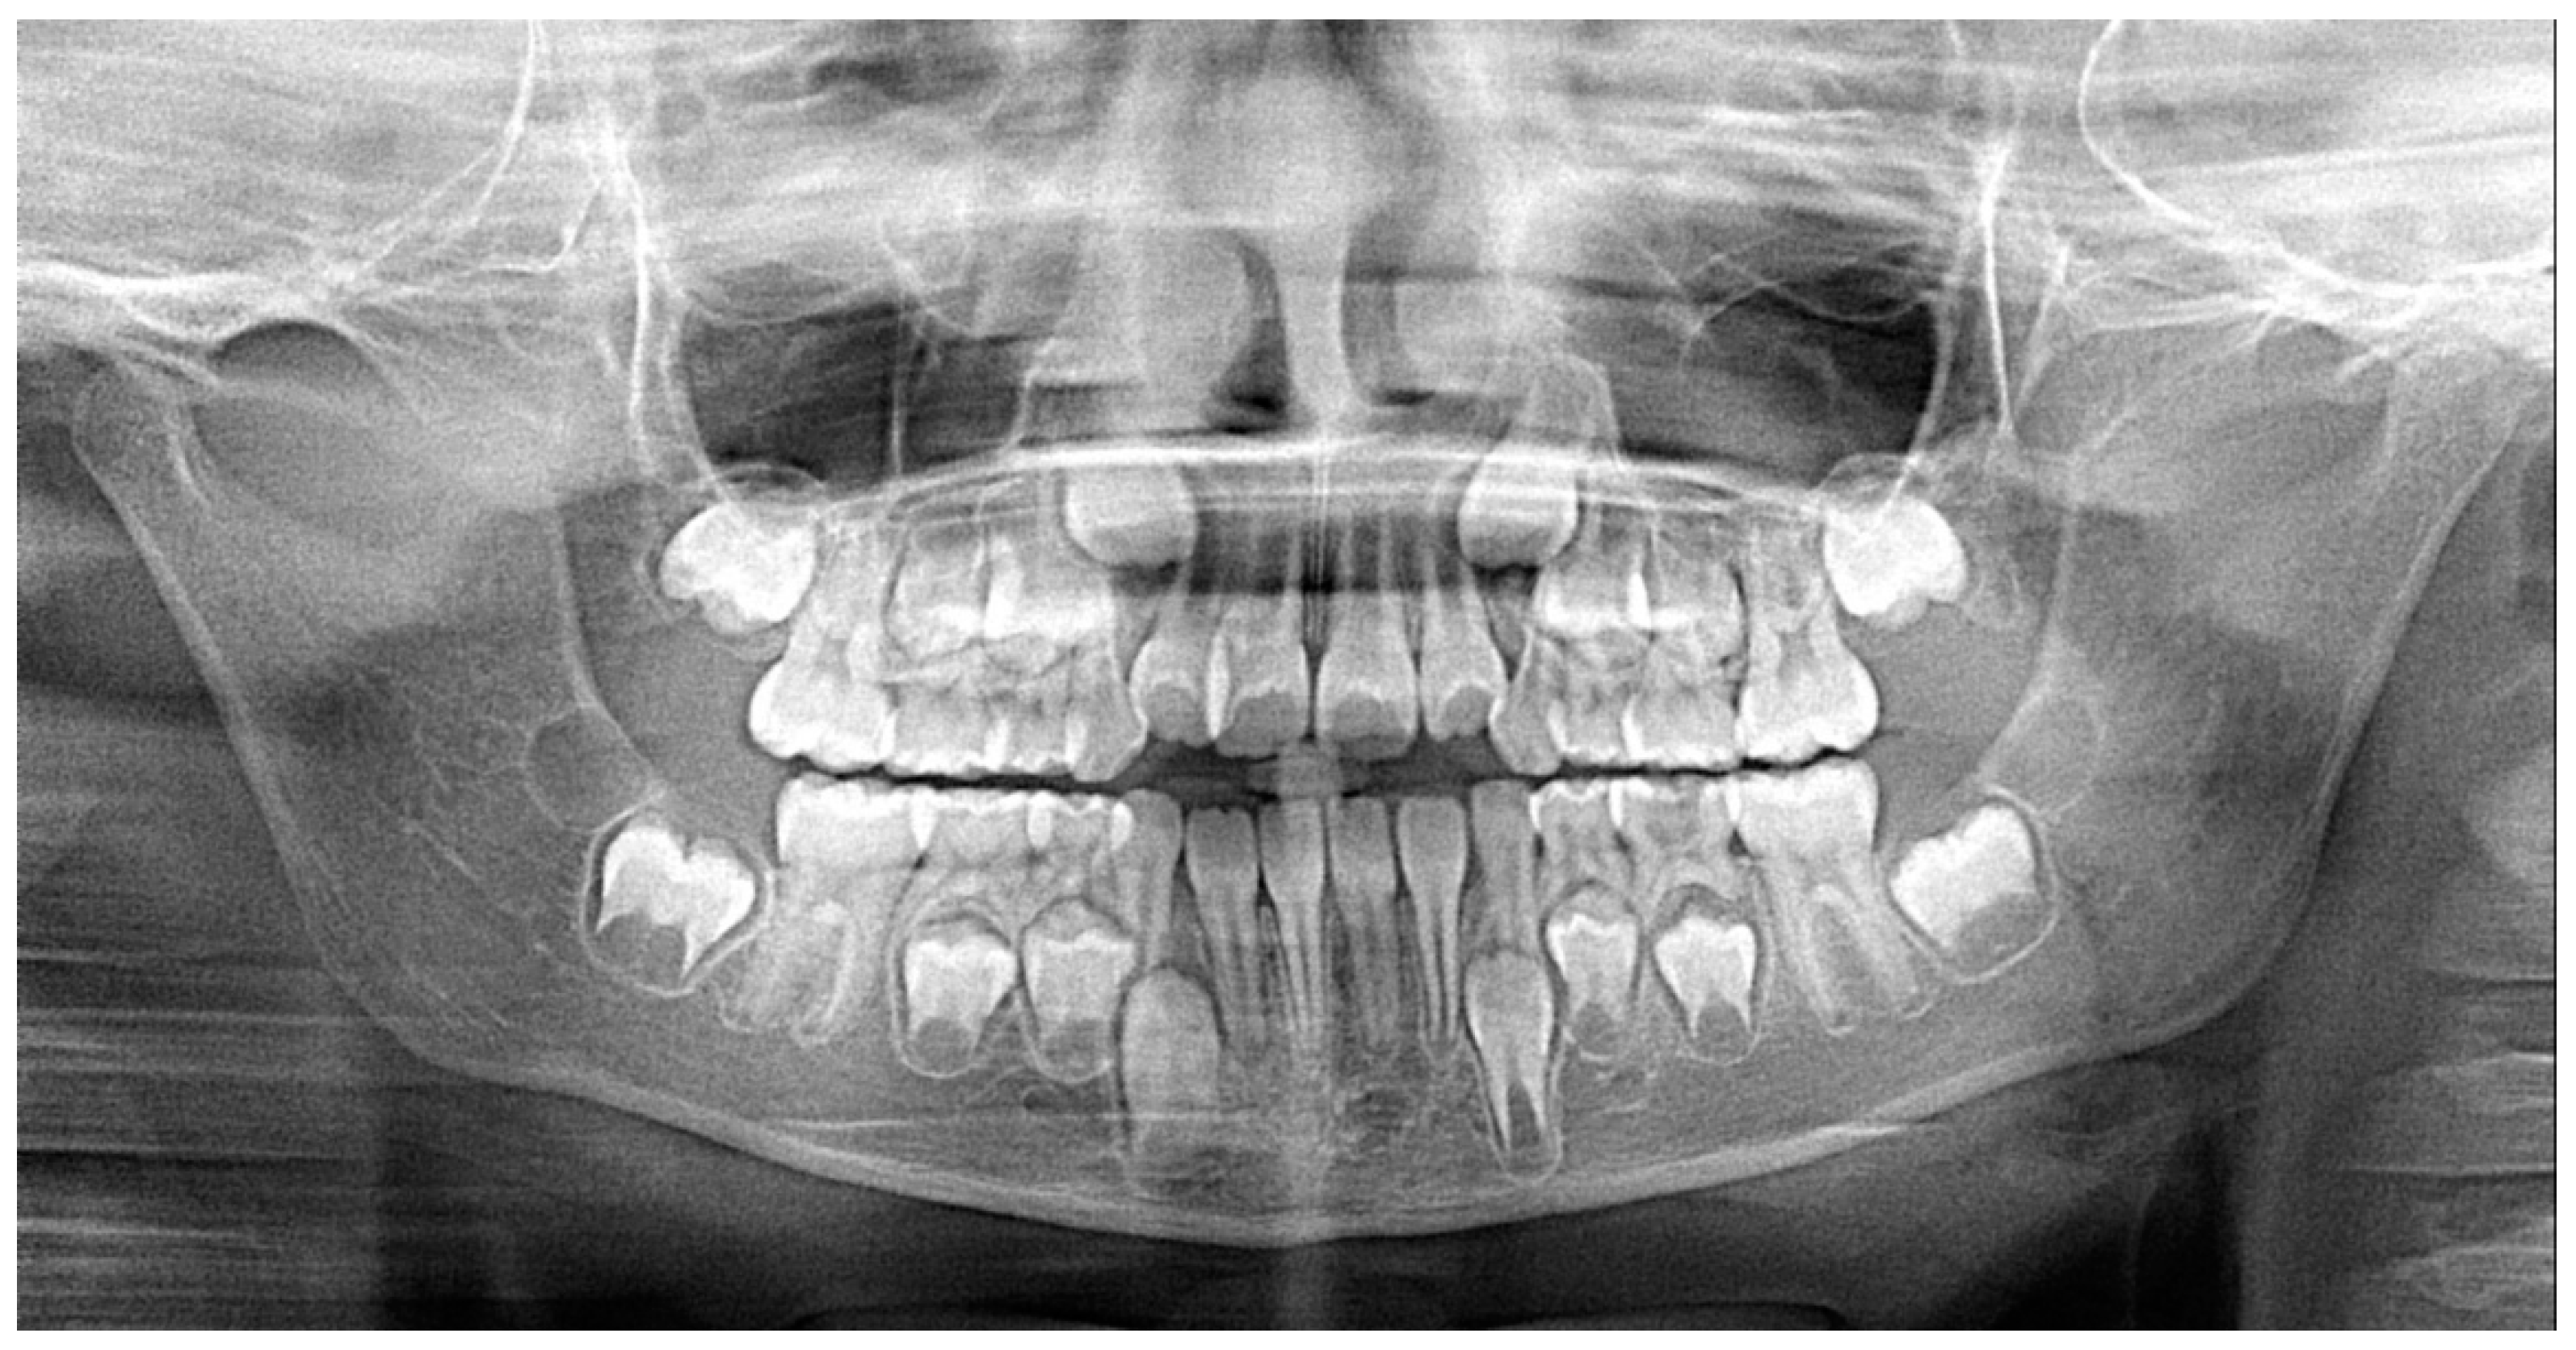

Panoramic radiograph showed the presence of all permanent dentition with no signs of ectopic eruptive pattern (Figure 5). We did not request lateral cephalogram considering the patient’s age and the absence of relevant clinical signs of skeletal antero–posterior discrepancies; thus, useless radiation exposure was avoided for the patient, according to the A.L.A.R.A. principle [20,21,22].

Figure 5.

Panoramic radiograph.